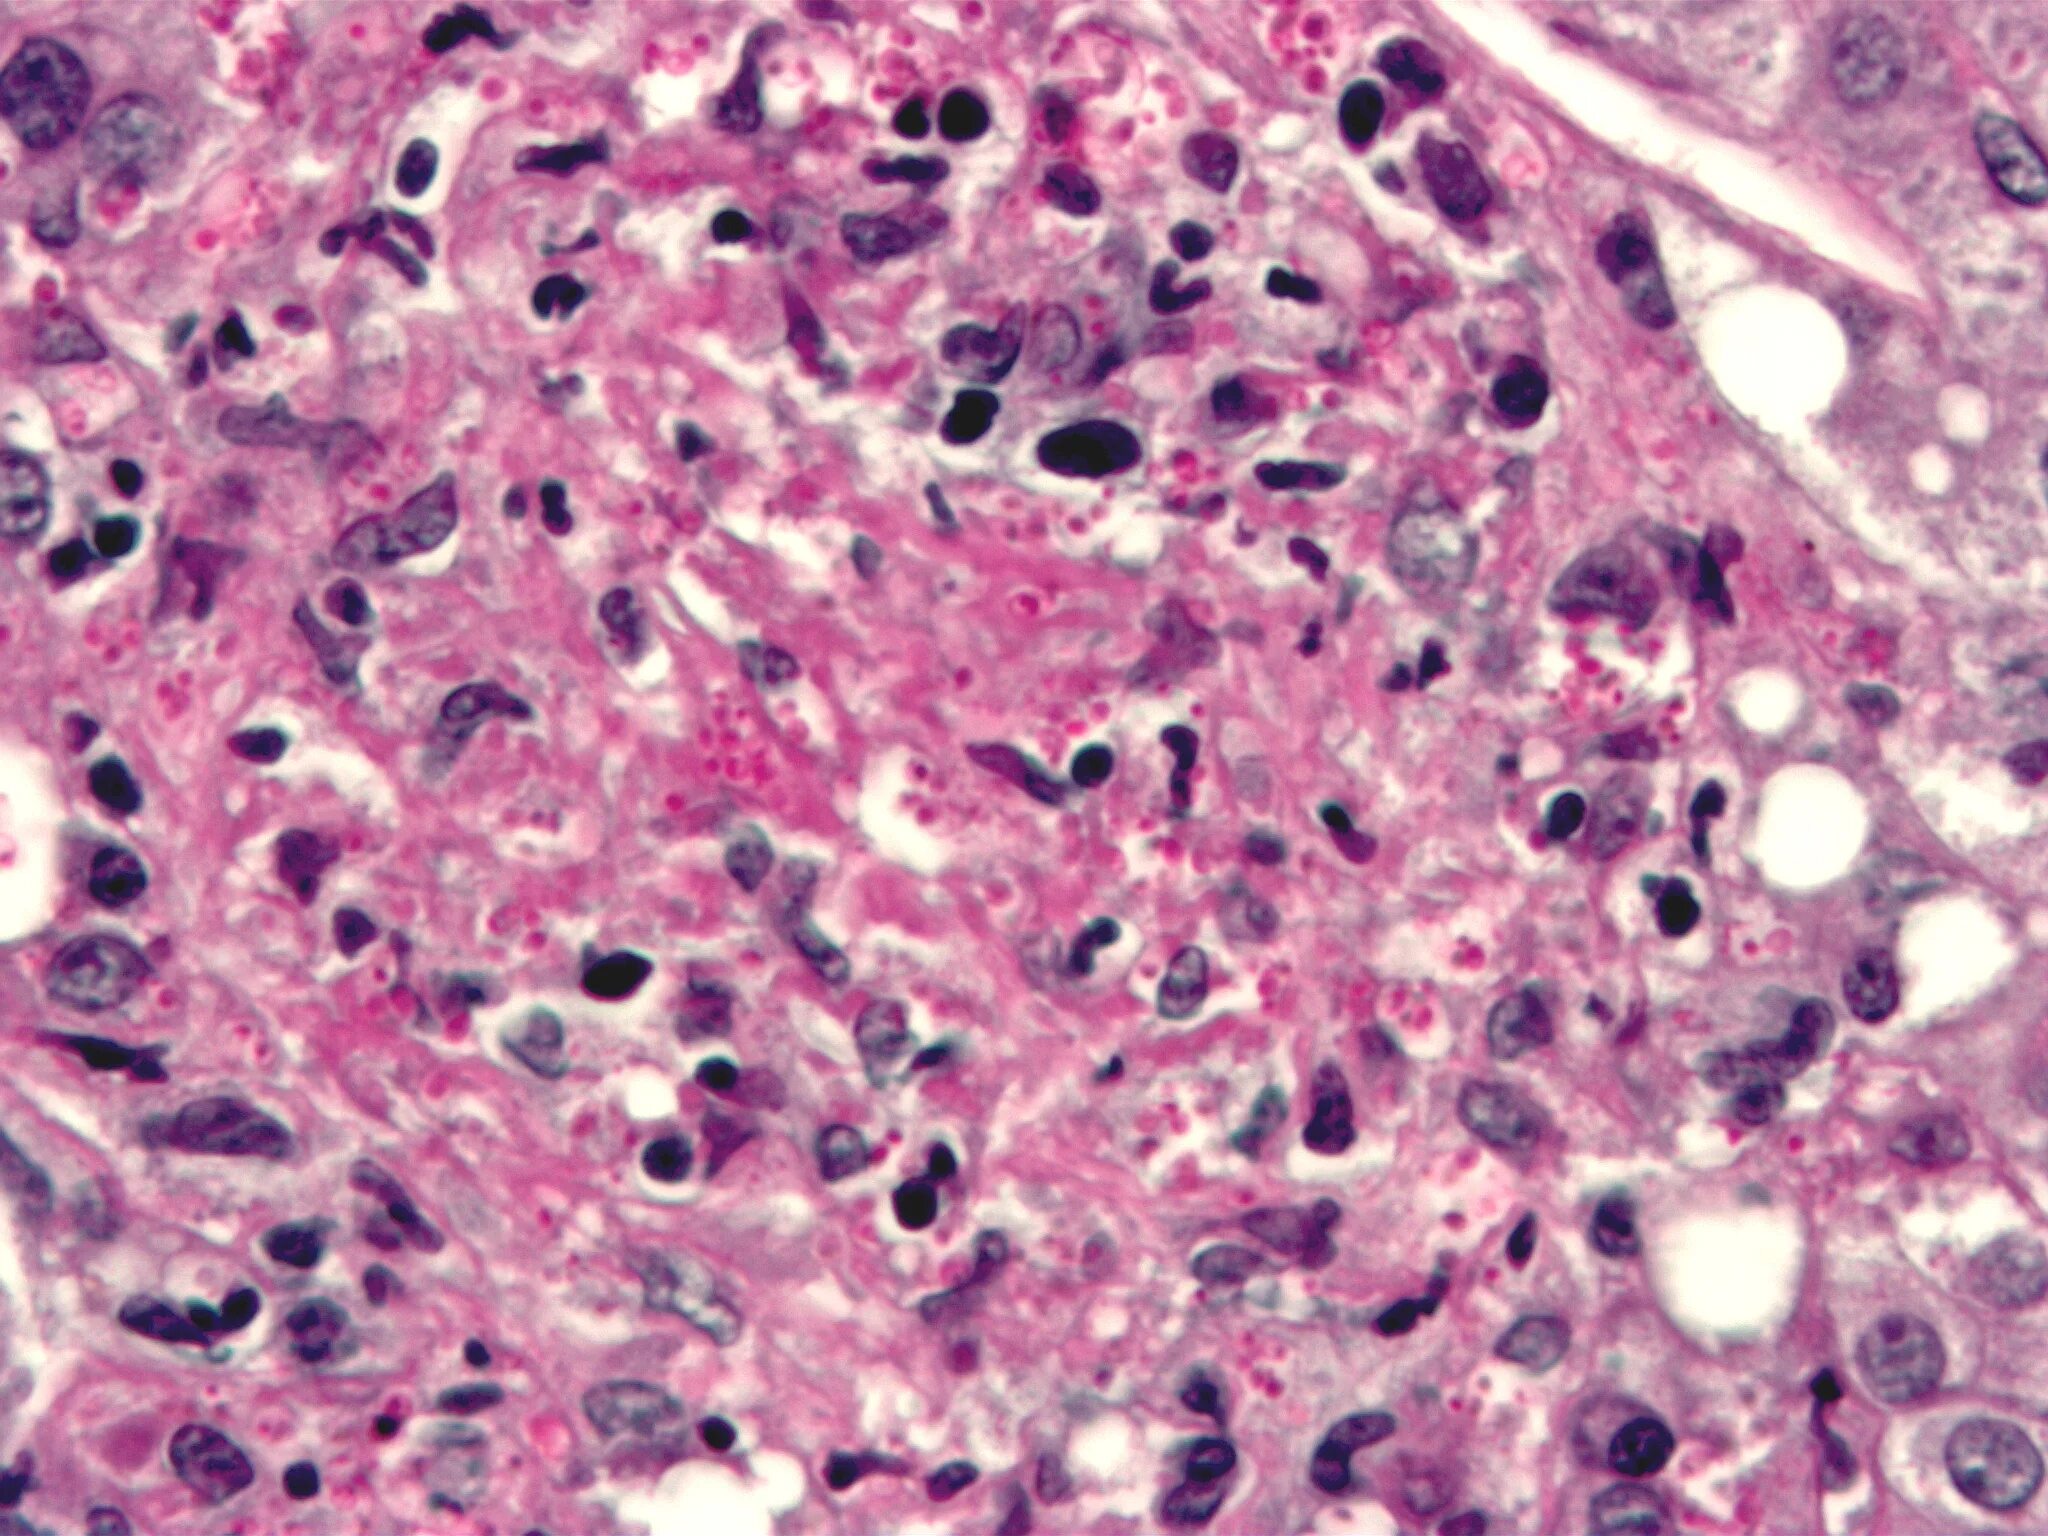

Гистоплазмоз это